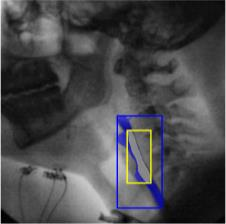

The videofluoroscopic swallowing study (VFSS) is a gold-standard imaging technique for assessing swallowing, but analysis and rating of VFSS recordings is time consuming and requires specialized training and expertise. Researchers have recently demonstrated that it is possible to automatically detect the pharyngeal phase of swallowing and to localize the bolus in VFSS recordings via computer vision, fostering the development of novel techniques for automatic VFSS analysis. However, training of algorithms to perform these tasks requires large amounts of annotated data that are seldom available. We demonstrate that the challenges of pharyngeal phase detection and bolus localization can be solved together using a single approach. We propose a deep-learning framework that jointly tackles pharyngeal phase detection and bolus localization in a weakly-supervised manner, requiring only the initial and final frames of the pharyngeal phase as ground truth annotations for the training. Our approach stems from the observation that bolus presence in the pharynx is the most prominent visual feature upon which to infer whether individual VFSS frames belong to the pharyngeal phase. We conducted extensive experiments with multiple convolutional neural networks (CNNs) on a dataset of 1245 bolus-level clips from 59 healthy subjects. We demonstrated that the pharyngeal phase can be detected with an F1-score higher than 0.9. Moreover, by processing the class activation maps of the CNNs, we were able to localize the bolus with promising results, obtaining correlations with ground truth trajectories higher than 0.9, without any manual annotations of bolus location used for training purposes. Once validated on a larger sample of participants with swallowing disorders, our framework will pave the way for the development of intelligent tools for VFSS analysis to support clinicians in swallowing assessment.